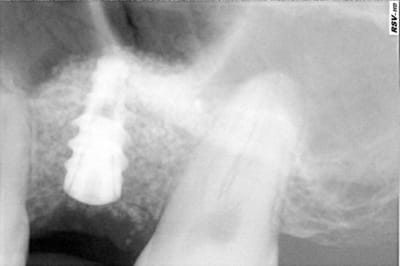

> avant d'envoyer le patient passer son cone-beam je n'étais pas convaincu que il

> y avait un kyste. comme quoi!

Sur la retro, on voit bien un manque de densité...